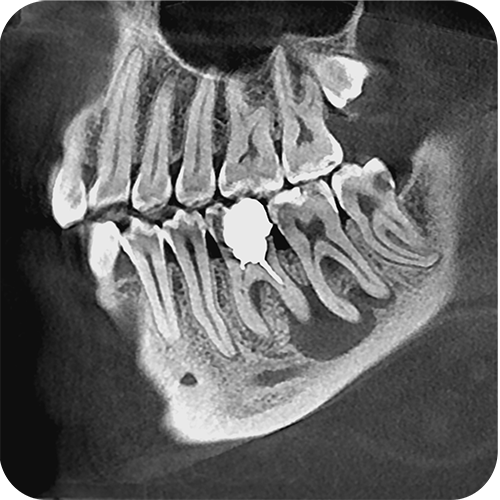

- Плоскопанельный детектор имеет самую высокую в классе разрешающую способность

756273e2623420e0e796d77f551404ab.png